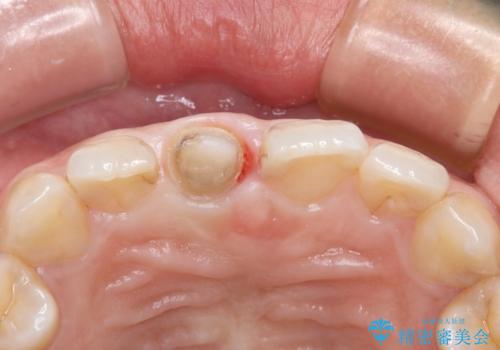

また、被せものと土台の境目が歯肉よりも上に見えていて、段差になっています。

そのため審美性、清掃性どちらの観点からもあまりよくない状態です。

不適合な被せものを除去し、土台の歯の形を修正し、精度の高いシリコーンによる型どりをしました。